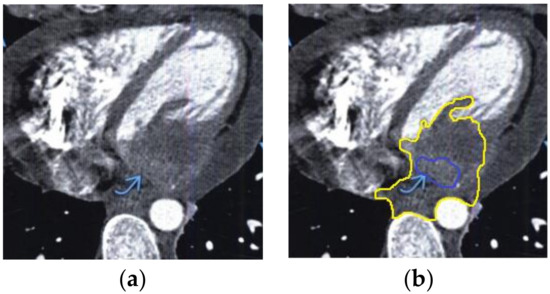

The contour extraction method was used to identify cancerous areas that, after applying the model to eliminate mixed noise, had an increased contrast of volumetric heterogeneous formations in the region of the heart [27]. This method was developed by the authors when analyzing thermal images to assess the condition of the coronary vessels of the myocardium under cardiopulmonary bypass. The contours of the cancerous regions in the examples used for applying the model to eliminate mixed noise (Figure 4, Figure 5, Figure 6, Figure 7, Figure 8 and Figure 9) are highlighted in yellow and they represent the visual boundary of the distribution of volumetric heterogeneous formations.

• For a patient with myxoma in the left atrium: during MRI with contrast enhancement in the left atrium, a hypodense mass formation, which causes mitral valve stenosis, was visualized (Figure 9).

Figure 9. Heart MRI: (a) image with white noise and (b) denoised image with contrast enhancement of the myxoma in the left atrium.